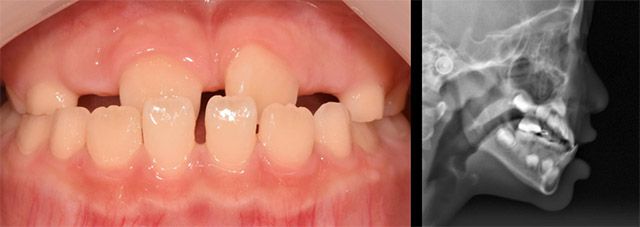

대표적인 경우가 위턱보다 아래턱이 앞으로 나와 윗니와 아랫니가 거꾸로 물리게 되는 ‘반대교합’이다. 반대교합은 만 7~8세 경 영구치가 맹출하는 시기에 주로 치료하지만, 정도가 심한 경우 유치열기(생후 6개월로부터 최초 영구치가 나타나기 직전까지의 기간)에도 치료한다.

이 교수는 “유치열기에는 아래턱보다 위턱의 성장이 중요하다”라며, “반대교합이 있으면 아래턱이 위턱의 성장을 방해하므로 위턱 성장을 촉진하는 치료를 주로 진행한다”라고 말했다.

반대교합의 대표적인 치료 방법은 페이스 마스크다. 구강 내 고정식 장치를 장착하고 고무줄로 페이스 마스크를 연결해 착용하게 되는데, 치료 기간은 통상 6개월에서 1년 정도 소요된다. 페이스 마스크의 권장 착용 시간은 하루 12~14시간으로, 집에 있는 시간을 활용해 최대한 착용하도록 권한다.